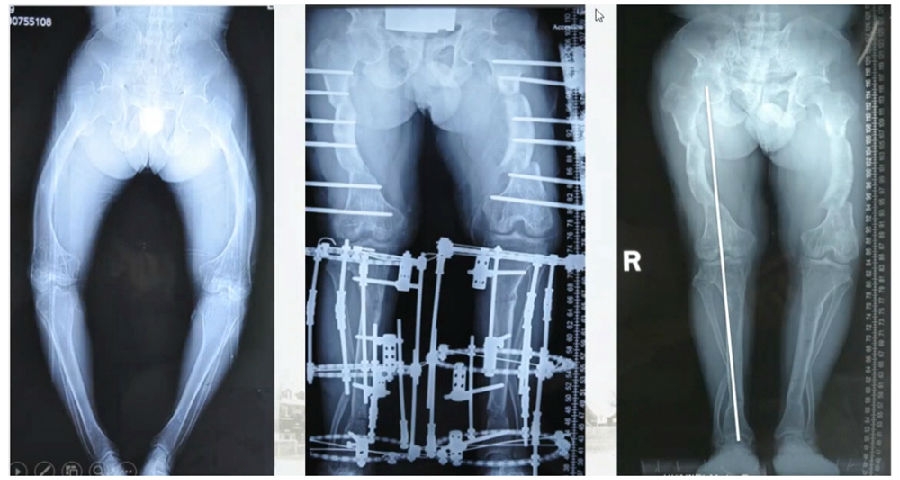

典型病例2,男性,52岁,双膝疼痛,低磷佝偻病,复合畸形。

术前

股骨畸形即时矫正,胫骨畸形缓慢矫正。

术中

手术前后对比

手术前后外观